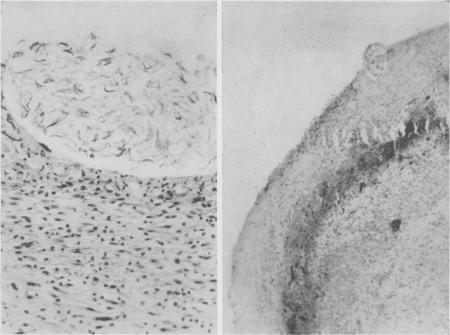

Meconium peritonitis.

Ann Surg. 1951 Apr;133(4):548-54. doi: 10.1097/00000658-195104000-00015.